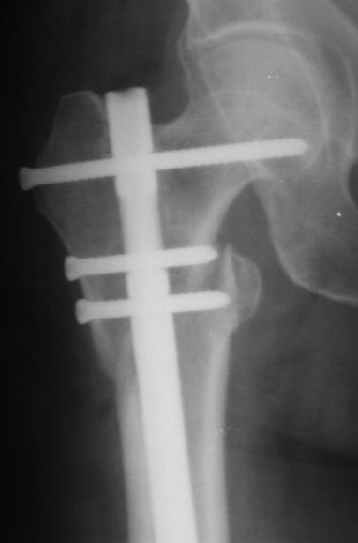

В частности, на проксимальном конце сделано еще одно дополнительное статическое отверстие. Можно ввести в проксимальном отделе 4 винта, из них 3 статические (2 в круглые отверстия и 1 по нижнему краю овального). Картинки в приложении. На дистальном конце стержня тоже кое-что улучшено. Спрашивайте в аптеках, как говорится. Выпускается предприятием "ЦИТО" (Москва), то есть это малобюджетное решение.

Конечно, мы не синтезируем остеопорозые вертельные переломы согласно прилагаемому примеру, винты 6 мм вырежутся. Но у более молодых при хорошем качестве кости такие или подобные гвозди с поперечным расположением винтов вполне применимы для меж- и подвертельных переломов.

Женя, эта картинка показывает не оптимальное лечение вертельных переломов в моем представлении, а особенности дизайна упомяутого фиксатора.

В частности, его возможности при фиксации переломов проксимального отдела бедра - в сравнении с другими, имеюшими лишь по одному статическому и динамическому отверстию и с кондуктором для введения 2 винтов.

Это было года 2,5 назад, мы тогда еще уточняли возможности шинирования с угловой стабильностью гвоздем с поперечным расположением винтов при переломах проксимального отдела бедра. Пациенту не пришлось приобретать намного более дорогой рекон или проксимальный гвоздь. В приложении еще несколько примеров применения того гвоздя при высоких переломах бедра, в том числе с более латеральной точкой входа. Гвоздь изгибаем для этого.